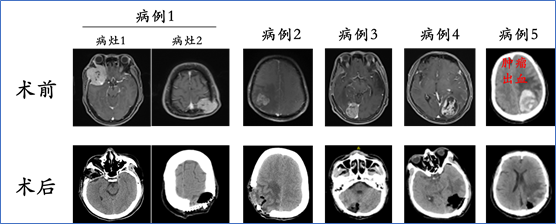

1. 肿瘤切除手术

目的:根治肿瘤,解除肿瘤压迫、促进神经功能恢复;

适应症:单发/寡转移灶,占位效应明显的脑转移灶;多发脑转移,颅内压力极高,症状明显-责任病灶明确;多发脑转移,肿瘤位于小脑、邻近脑干等重要功能区部位,有压迫脑干或者导致梗阻性脑积水的趋势或风险;合并肿瘤出血;局限性颅骨转移。

肝癌脑转移瘤切除手术病例